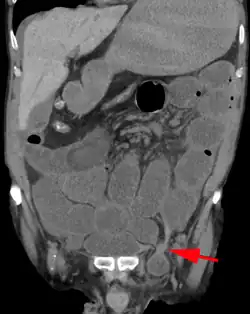

An incarcerated inguinal hernia as seen on cross sectional CT scan

There are two types of inguinal hernia, direct and indirect, which are defined by their relationship to the inferior epigastric vessels. Direct inguinal hernias occur medial to the inferior epigastric vessels when abdominal contents herniate through a weak spot in the fascia of the posterior wall of the inguinal canal, which is formed by the transversalis fascia. Indirect inguinal hernias occur when abdominal contents protrude through the deep inguinal ring, lateral to the inferior epigastric vessels; this may be caused by failure of embryonic closure of the processus vaginalis.